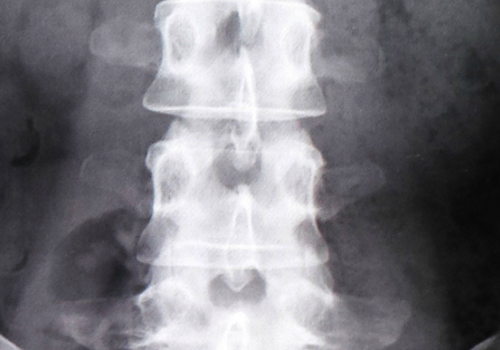

まず最初に、腰痛やヘルニアには特効薬は無く

レントゲン等でも原因の85%は特定でき無いとも言われております。